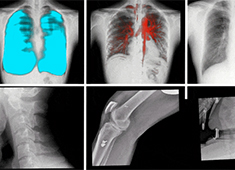

三维重建技术在医学影像诊断中的应用价值三维重建技术在医学影像诊断中的应用非常广泛,主要包括以下几个方面:1.诊断疾病:通过三维重建技术,医生可以更直观、清晰地观察到患者体内的异常情况,如肿瘤、骨折等,从而更准确地诊断疾病。... 发布时间:2024-08-22 16:54:00